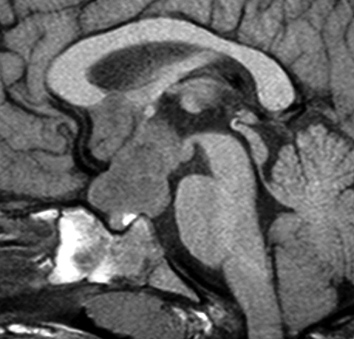

幼児の視路の毛様粘液性星細胞腫です。T2強調画像(左側)で白く高信号に写るのが特徴です。ガドリニウム増強ではまだらになっていますが,均一に真っ白に高信号になることも多いです。乳幼児のものは,ドロドロに柔らかい腫瘍です。

whole optic pathway pilocytic astrocytomaとは

両側の眼窩内視神経から視交叉、視索,外側膝状体,内包後脚,視放線近位部までが腫瘍化しています。FLAIRで高信号で,不規則にガドリニウム増強されます。これを手術摘出したり生検したりしても無駄です。放射線治療は不可能であり治療方法は化学療法のみです。

化学療法が有効なのは,上の画像のようにガドリニウム増強で強く増強されるタイプです,またT2強調画像で強い高信号になるものほど化学療法が有効です,要するに毛様粘液性星細胞腫の要素に化学療法が有効であるということです

この毛様細胞性星細胞腫はガドリニウムでほとんど増強されません(右側のMRI)から,化学療法を行っても小さくなりませんので,手術摘出する必要があります,実際に視床下部から発生したもの視交叉が犯されておらず,手術亜全摘出できました